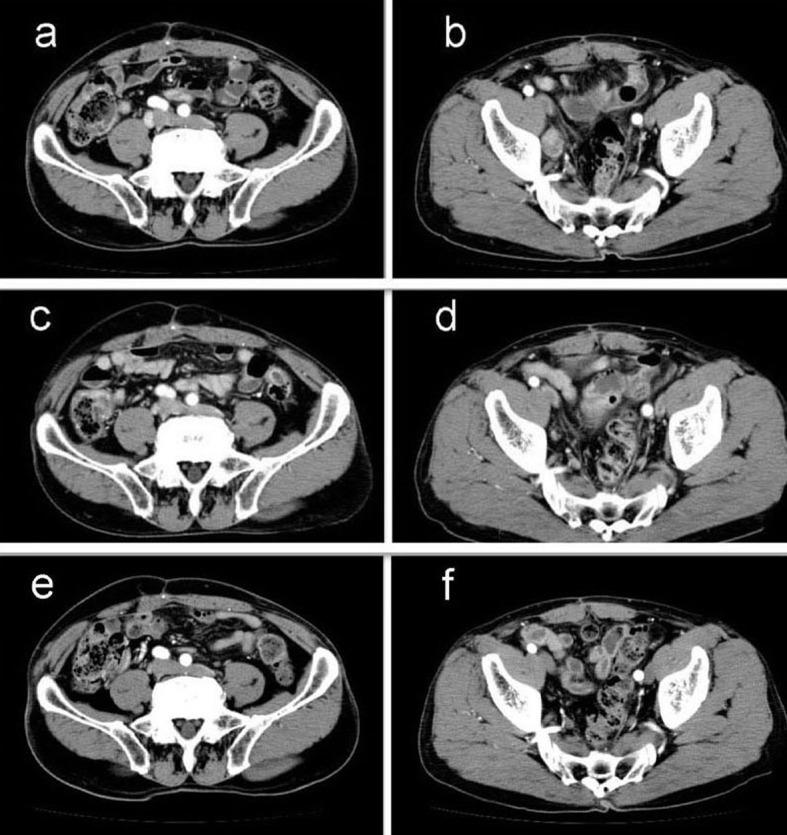

This report presents a case of para-aortic and lateral pelvic lymph node recurrence of rectal cancer that showed complete response to S-1 monotherapy. A 69-year-old man underwent low anterior resection for rectal cancer in 2007. Para-aortic lymph and right lateral pelvic lymph node recurrence occurred in 2008. He received a fluorouracil/folinic acid plus oxaliplatin regimen; however, G4 neutropenia and G3 fatigue were experienced. We started S-1 monotherapy as a salvage treatment. Abdominal computed tomography did not reveal any para-aortic and lateral pelvic lymph nodes recurrence after 10 cycles of S-1 monotherapy. Hence, response in this case was classified as a complete response. No recurrence was noted 36 months after the complete response. S-1 monotherapy is likely to be effective in treating patients with metastatic colorectal cancer who do not respond to standard combination chemotherapy.

摘要